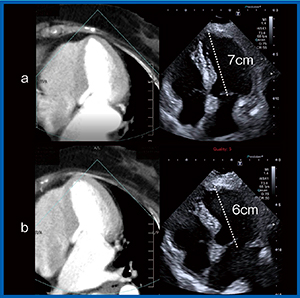

実際に,心尖部を適切に描出できた画像(図3 a)とできなかった画像(図3 b)を比較してみると,適切な画像では弁輪部からの距離が7cm,適切でない画像では6cmと,10%以上のズレがあった。こうしたズレは,左室容積やEFの計測結果の大きな誤差につながるため,2つの画像の違いをしっかりと確認できることは大変有用である。

図3 心尖部像の描出におけるFusion Imagingの

教育的効果